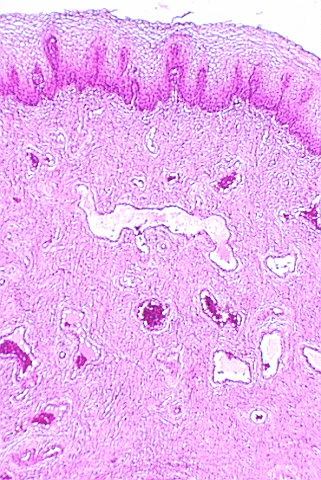

A low magnification view of the vagina is shown in this photograph. The epithelium is stratified squamous. Underneath the epithelium is a lamina propria. Note that there is no muscularis mucosa. You will use this feature to distinguish the vagina from the esophagus. Another difference is the fact that the vagina has some tight junctions which, along with a lipid secretory material, make the epithelium a permeability barrier.

The vagina wall has no glands and so lubrication must come from the cervix and glands around the opening of the urethra.

The muscle coat in the vaginal wall is interlacing bundles of smooth muscle. There is a thin circumferential band of striated muscle around the ostium of the vagina.

The following figure is from your slide 84, showing a section of the vagina. Note the pale epithelia which are washed out probably because they contain glycogen and lipid.

In the basal regions of the vagina epithelium, one may see lymphocytes and Langerhans cells. What important function (s) do the Langerhans cells play?